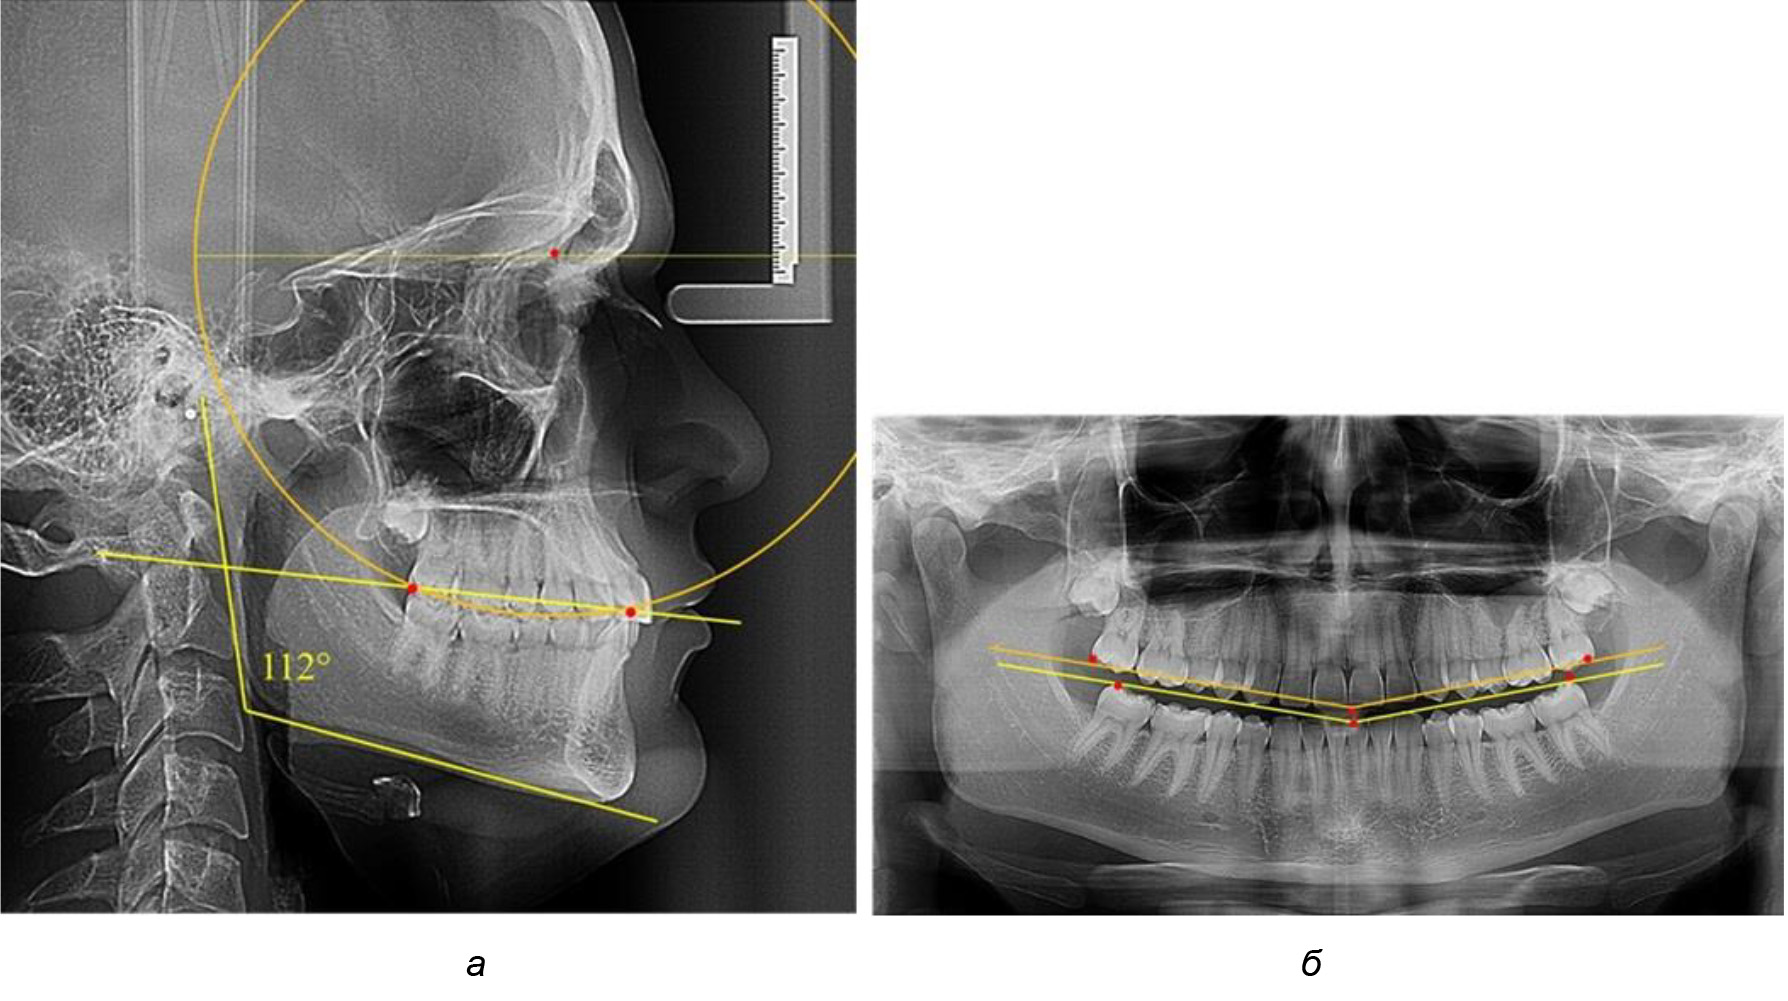

Рис. 5. Особенности ТРГ при патологической кривой Spee до лечения (а) и после лечения (б) техникой «прямой» дуги

Рис. 6. Особенности ТРГ при оптимальной кривой Spee до лечения (а) и после лечения (б) техникой «прямой» дуги

Глубина кривой Spee в среднем по 2-й подгруппе составила (5,69 ± 1,57) мм, что было достоверно больше, чем у людей с физиологической окклюзией (р ˂ 0,05). Достоверных различий с показателями, полученными при анализе ТРГ и ОПТГ, нами не отмечено (р ˃ 0,05). Отношение радиуса окружности к сагиттальному размеру окклюзионной линии в среднем по подгруппе составляло 1,372 ± 0,042 и не соответствовало числу Фибоначчи, что может быть использовано в качестве диагностического критерия определения патологической формы кривой Spee. После лечения пациентов техникой «прямой» дуги было отмечено незначительное увеличение сагиттального размера окклюзионной лини в среднем на (2,12 ± 0,77) мм. Однако окклюзионная линия практически касалась окклюзионного контура всех жевательных зубов, и отмечалось практически полное отсутствие кривой Spee.

Таким образом, проведенное лечение техникой «прямой» дуги способствует нормализации окклюзионного равновесия и торку передних зубов, однако не соответствует оптимальному окклюзионному статусу, характеризующему физиологическую окклюзию. При этом величина нижнечелюстного угла оставалась на прежнем уровне (рис. 5).

Обращает на себя внимание, что глубина кривой Spee в анализируемой подгруппе практически не отличалась от показателей, полученных у людей с физиологической окклюзией, и составляла (4,23 ± 1,58) мм. Отношение радиуса окружности к сагиттальному размеру окклюзионной линии в среднем по подгруппе составляло 1,623 ± 0,02 и соответствовало числу Фибоначчи.

После лечения пациентов техникой «прямой» дуги, так же как и в 1-й подгруппе, было отмечено увеличение сагиттального размера окклюзионной лини в среднем на (2,38 ± 0,83) мм. Окклюзионная линия практически касалась окклюзионного контура всех жевательных зубов, и отмечалось практически полное отсутствие кривой Spee, так же как и у людей 1-й подгруппы 2-й группы (рис. 6).

Таким образом, проведенное лечение техникой «прямой» дуги способствует нормализации окклюзионного равновесия и торку передних зубов, однако не соответствует оптимальному окклюзионному статусу, характеризующему физиологическую окклюзию. При этом величина нижнечелюстного угла оставалась на прежнем уровне.